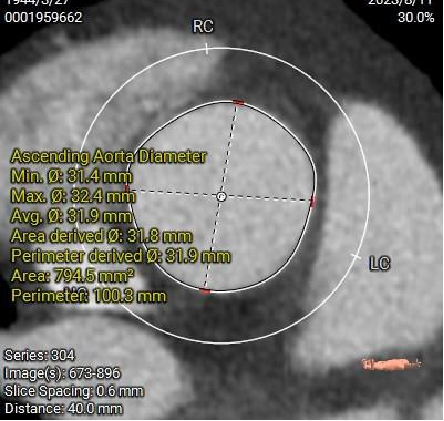

AA31.9mm